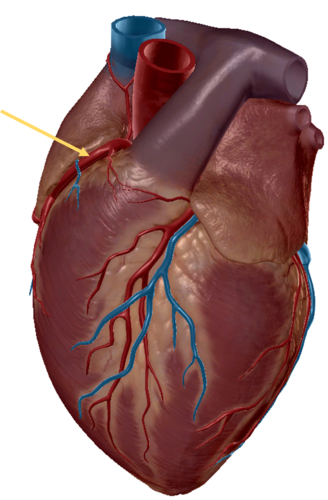

right coronary artery

circumflex artery

atrevoventricullar sulus

anterior inter ventricular sulcus